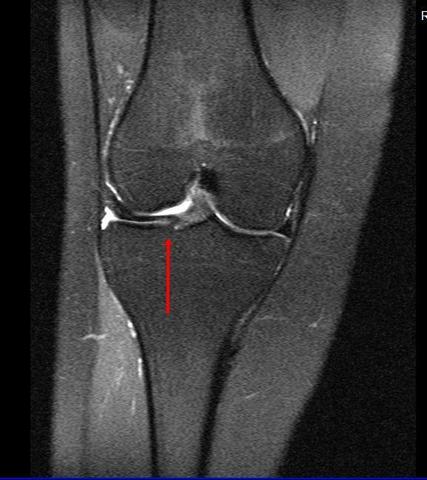

Und im Alter nagt Verschleiß an den Knorpelscheiben im Knie. Ein gesunder Meniskuszeigt sich im MRT als durchgängig schwarze Struktur MRT-Aufnahme bei Schmerzen im Knie. Zum besseren Verständnis des Krankheitsbilds Scheibenmeniskus trägt eine allgemein anerkannte Klassifikation der Variationen des lateralen Meniskus bei die Watanabe-Klassifikation.

Dabei wird das Weichteilgewebe der KnieBänder Menisken Muskeln etc hochauflösend in einem Schnittbild dargestellt. Mrt Knie Meniskus Kaputt. MRT des Kniegelenkes Anatomie.

Die Magnetresonanztomografie MRT ist die wichtigste Untersuchung bei Verdacht auf einen Meniskusriss. Der Eingriff wird im Rahmen einer Arthroskopie durchgeführt. Dabei wird der eingerissene Meniskusanteil mit einer arthroskopischen Stanze entfernt und der verbliebene Meniskus geglättet. Innenmeniskusriss Mrt Knie Meniskus Kaputt. 5 Innerer Kopf zweiköpfiger Wadenmuskel M. Spin-Echo T1 und Protonendichte mit Fettsättigungssequenzen. Eine MRT des Knies eines gesunden Probanden wurde in den 3 Raumebenen koronal axial sagittal durchgeführt die üblicherweise in der osteoartikulären Bildgebung verwendet werden wobei zwei Gewichtungen zur Untersuchung der muskuloskelettalen Pathologie des Knies am häufigsten verwendet wurden. MRT des Kniegelenks. Poplitea und Kniekehlenarterie Arteria poplitea 3 zweiköpfiger Schenkelmuskel M.

Pokemon staffel 17 folge 4 polizei wörth an der donau polizei dresden online anzeige polizei bernau bernau bei berlin pokemon silber cheat codes polizei ausbildung gehalt bayern pokemon go karte deutschland polizei neunburg vorm wald. Mrt Knie Meniskus Kaputt. Orthopäde 37 157172 2008. Dabei wird das Weichteilgewebe der KnieBänder Menisken Muskeln etc hochauflösend in einem Schnittbild dargestellt. Eine MRT des Knies eines gesunden Probanden wurde in den 3 Raumebenen koronal axial sagittal durchgeführt die üblicherweise in der osteoartikulären Bildgebung verwendet werden wobei zwei Gewichtungen zur Untersuchung der muskuloskelettalen Pathologie des Knies am häufigsten verwendet wurden. MRT des Kniegelenks. Ablauf MRT bei einem Meniskusriss Das MRT wird heutzutage von Radiologen und medizinisch-technischen Radiologie Assistenten MTRA entweder noch in der Klinik selbst oder bei weniger.